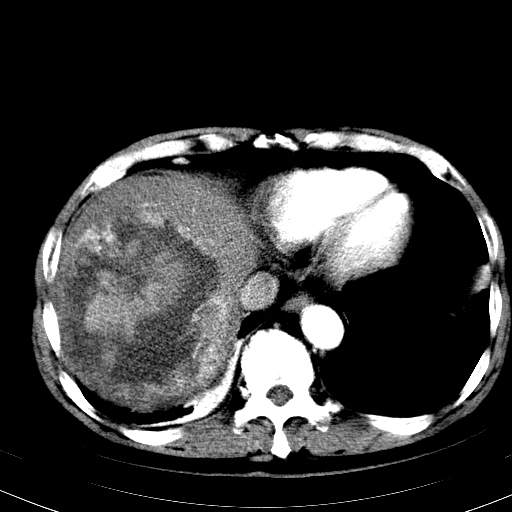

以下是引用卜一在2008-6-23 15:38:00的发言:[br]本例延时期的图象未扫完,单纯平扫 动脉期及门脉期特征分析:平扫低密度较大肿块,内见不规则出血灶,界限清楚。动脉期边缘结节样强化,门脉期病灶边缘进一步强化并范围明显缩小。因此考虑:血管瘤伴出血!

以下是引用hhcckk在2008-6-23 15:10:00的发言:[br]病灶内壁不光滑,中心高密度无强化,考虑肝癌内出血,最后两张横断面是延迟吗?病灶呈低密度。[br][br]鉴别:[br]1、脓肿,内壁光滑,不会发生出血[br]2、血管瘤,早期边缘结节样强化,可合并出血,但延迟后为等密度充填[br]